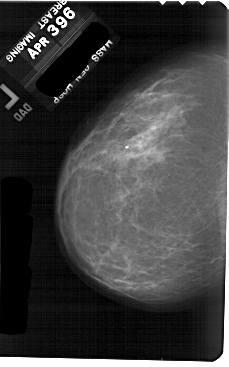

A_1886_1.LEFT_CC

LEFT_CC LINES 5491 PIXELS_PER_LINE 3421 BITS_PER_PIXEL 12 RESOLUTION 43.5 NON_OVERLAY